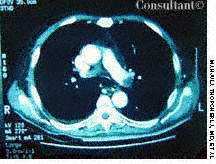

A 56-year-old man who had hematuria for 2 weeks underwent ultrasonography. This disclosed a well-circumscribed cyst in the lower pole of the left kidney and echogenic foci in the upper pole of the right kidney, without any evidence of posterior shadowing. A hyperechoic, well-circumscribed, circular focus was also seen in the right lobe of the liver. Abdominal CT confirmed the presence of a left renal cyst and revealed a 4.7-cm hypodense lesion in the right lobe of the liver, which suggested hemangioma.